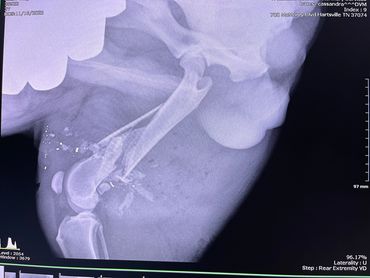

We were working outside, and a couple of our dogs were playing in the yard. It was starting to get dark when we heard a bunch of coyotes followed by a gun shot. We live in the middle of nowhere so these types of things aren’t unusual, but this time the sounds were uncomfortably close. The dogs were quick to come back up to the house, but Hugo was no where to be found. We hollered for him for hours. It was 22 degrees that night, and Hugo hates the cold, but he never came home. We searched the woods for hours the next morning. Nothing. We took to local Facebook groups to find him with no luck. When Shanda came home from work that Tuesday, Hugo was standing at the top of our driveway. He was beat up pretty bad, his hind leg was swollen, overall he seemed ok, but most importantly he was alive! THANK GOD! Jamie took him to the vet the following morning, and we learned that he had actually been shot by a muzzleloader. The bullet entered the back of his hind leg, come out the front of his leg, reentered his stomach, and stopped at his chest. The injury to his leg was too severe for our vet to repair, and with so many other question marks remaining, we had no choice but to amputate. He had lost a lot of blood and was possibly bleeding internally so we had to put the surgery off several days to get his blood count up. He spent eight days at the vet trying to stabilize his body before they were comfortable enough to do the amputation and fix the hernia where the bullet reentered his stomach. The vet was not able to remove the bullet from his chest without fear of it moving further into his chest cavity. A few days after surgery, we finally got to bring our big guy home! He’s doing very well and is adjusting quickly. It’s truly a miracle! We pray that the muscles around the bullet heal and keep the bullet in place to avoid any further complications. Right now we are just thankful that our baby is home and alive!